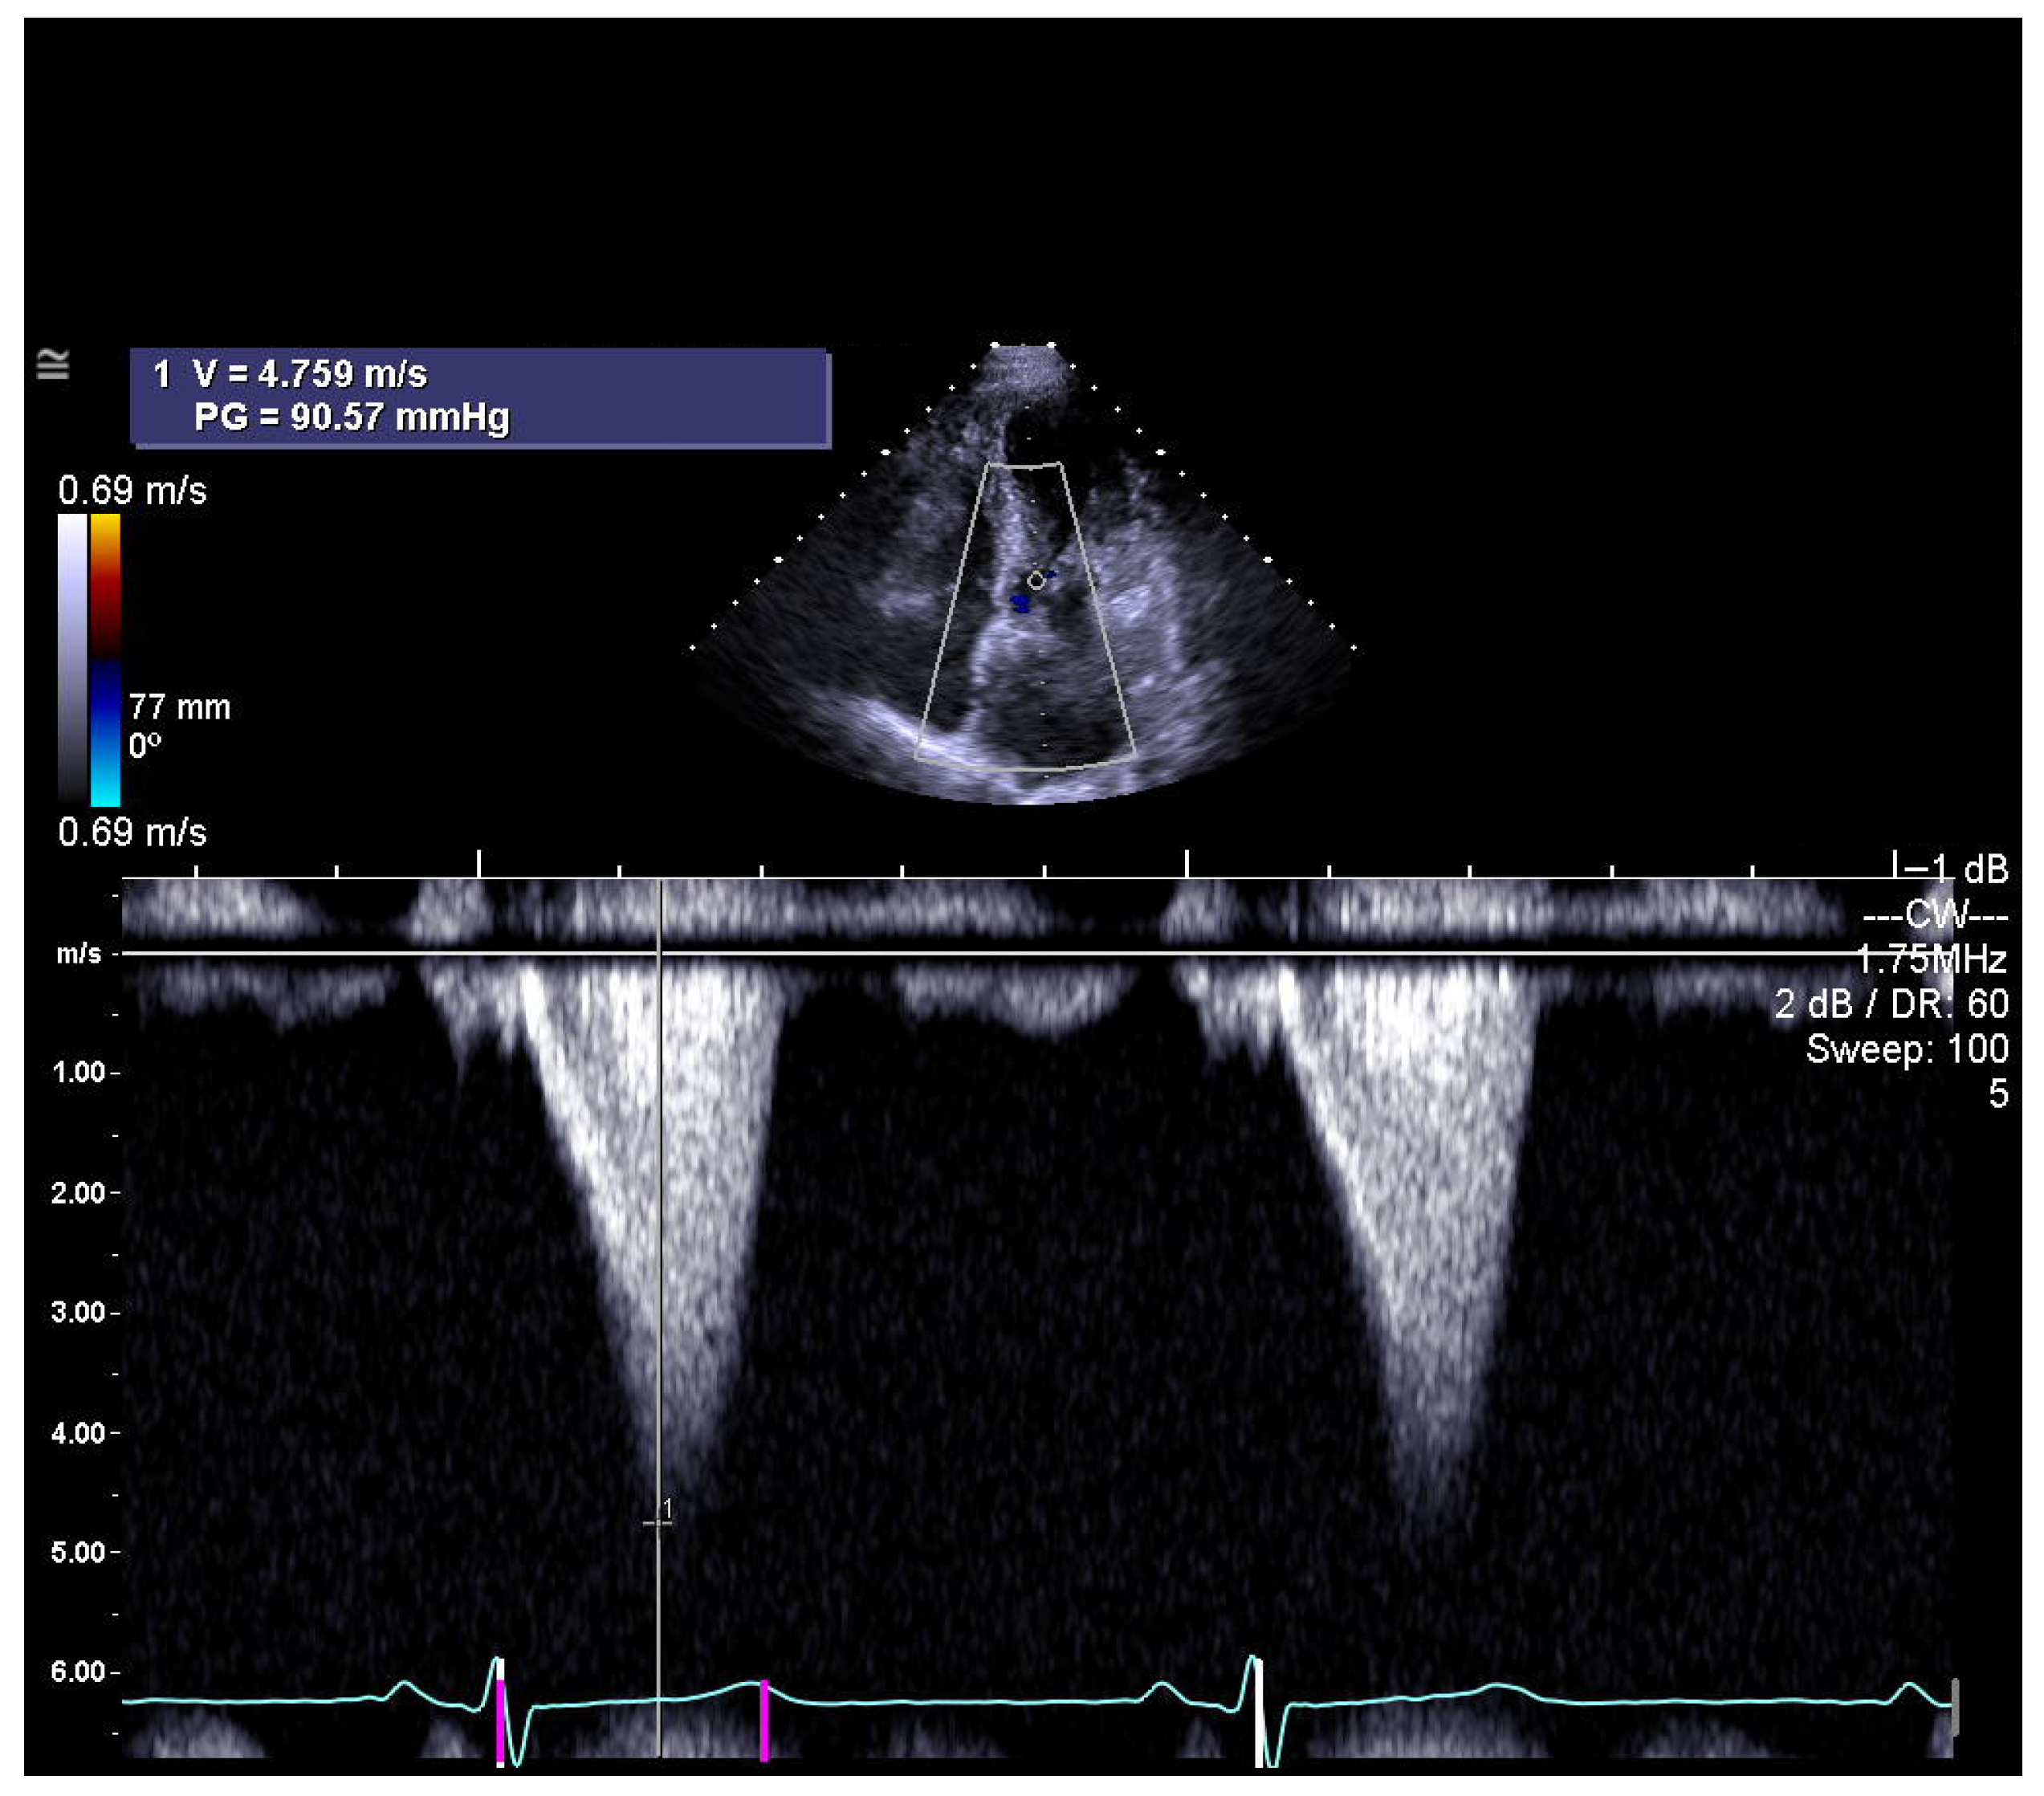

Global guidelines emphasize that septal reduction therapy (SRT) should only be performed in high-volume, specialized centers with experienced multidisciplinary heart teams to ensure the best outcomes. There is strong consensus regarding its indications in patients with obstructive hypertrophic cardiomyopathy. SRT is reserved for individuals who continue to experience significant symptoms—most often NYHA Class III–IV limitations such as severe shortness of breath or angina—despite optimal or maximally tolerated medical therapy. Across all recommendations, a peak left ventricular outflow tract (LVOT) gradient of ≥50 mmHg, whether at rest or during physiologic provocation, is considered essential (Figure 1). Additional requirements include systolic anterior motion (SAM) of the mitral valve and sufficient anterior septal thickness to allow safe procedural intervention. When determining the specific modality of SRT, guidelines consistently prefer surgical septal myectomy, especially for patients who also need surgical correction of other cardiac conditions. In cases where surgery is contraindicated or carries excessive risk, alcohol septal ablation (ASA) is endorsed as the alternative [1,2].

Figure 1. The left ventricular outflow tract (LVOT) shows a maximum gradient, usually with a late systolic peak, as assessed by continuous-wave Doppler echocardiography (photo and copyright: T.P.). PG—peak aortic valve gradient; V—maximum aortic valve velocity.